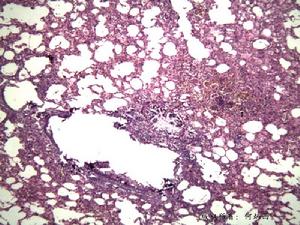

(3)粟粒結節型:為全身粟粒型結核的一部分,胃壁各層可見散在粟粒結節。

(4)炎症增殖型(瀰漫浸潤型):病變常累及胃壁各層,故胃壁增厚,黏膜呈息肉樣增生。3.組織形態病理病變附近的淋巴結常有腫大及乾酪樣壞死。病理組織學檢查可見典型的乾酪樣肉芽腫,常位於黏膜和黏膜下層,很少累及肌層。組織切片抗酸染色可發現抗酸桿菌。